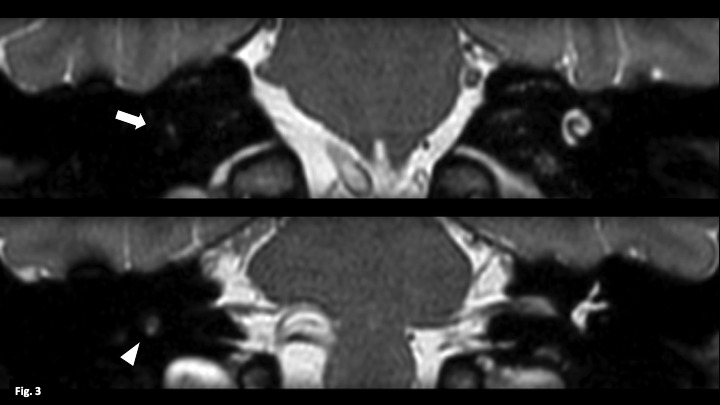

Labyrinthitis ossificans is a pathology consisting of calcification of the membranous labyrinth resulting in profound sensory deafness. It is usually due to an acute inflammatory process that progresses to ossification of the labyrinth. The clinical manifestations are irreversible hearing loss, dizziness and vomiting. It is diagnosed by computed tomography (CT) and magnetic resonance imaging (MRI). It is important to make the correct diagnosis before cochlear implantation, as ossification of the labyrinth can hinder or prevent the implantation of electrodes.